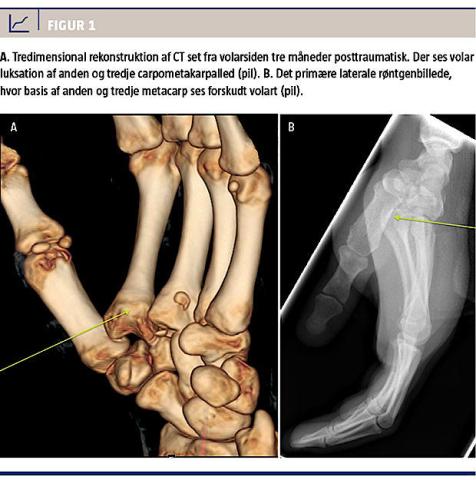

Ved kontrol tre måneder postoperativt bemærkede patienten, at håndryggen var sunket synligt, og der føltes mekanisk stop for tommelens opposition. En CT afslørede nu total volar luksation af anden metacarp og subluksation af tredje metacarp i forhold til den distale karpalrække (Figur 1A). Retrospektivt kunne dette ses på det primære røntgenbillede (Figur 1B). Ved efterfølgende operation sås store bruskskader på ledfladerne. Det lykkedes ved kraftfuld manipulation at reponere begge CMC-led, og de blev transfikseret med tre K-tråde i ni uger.